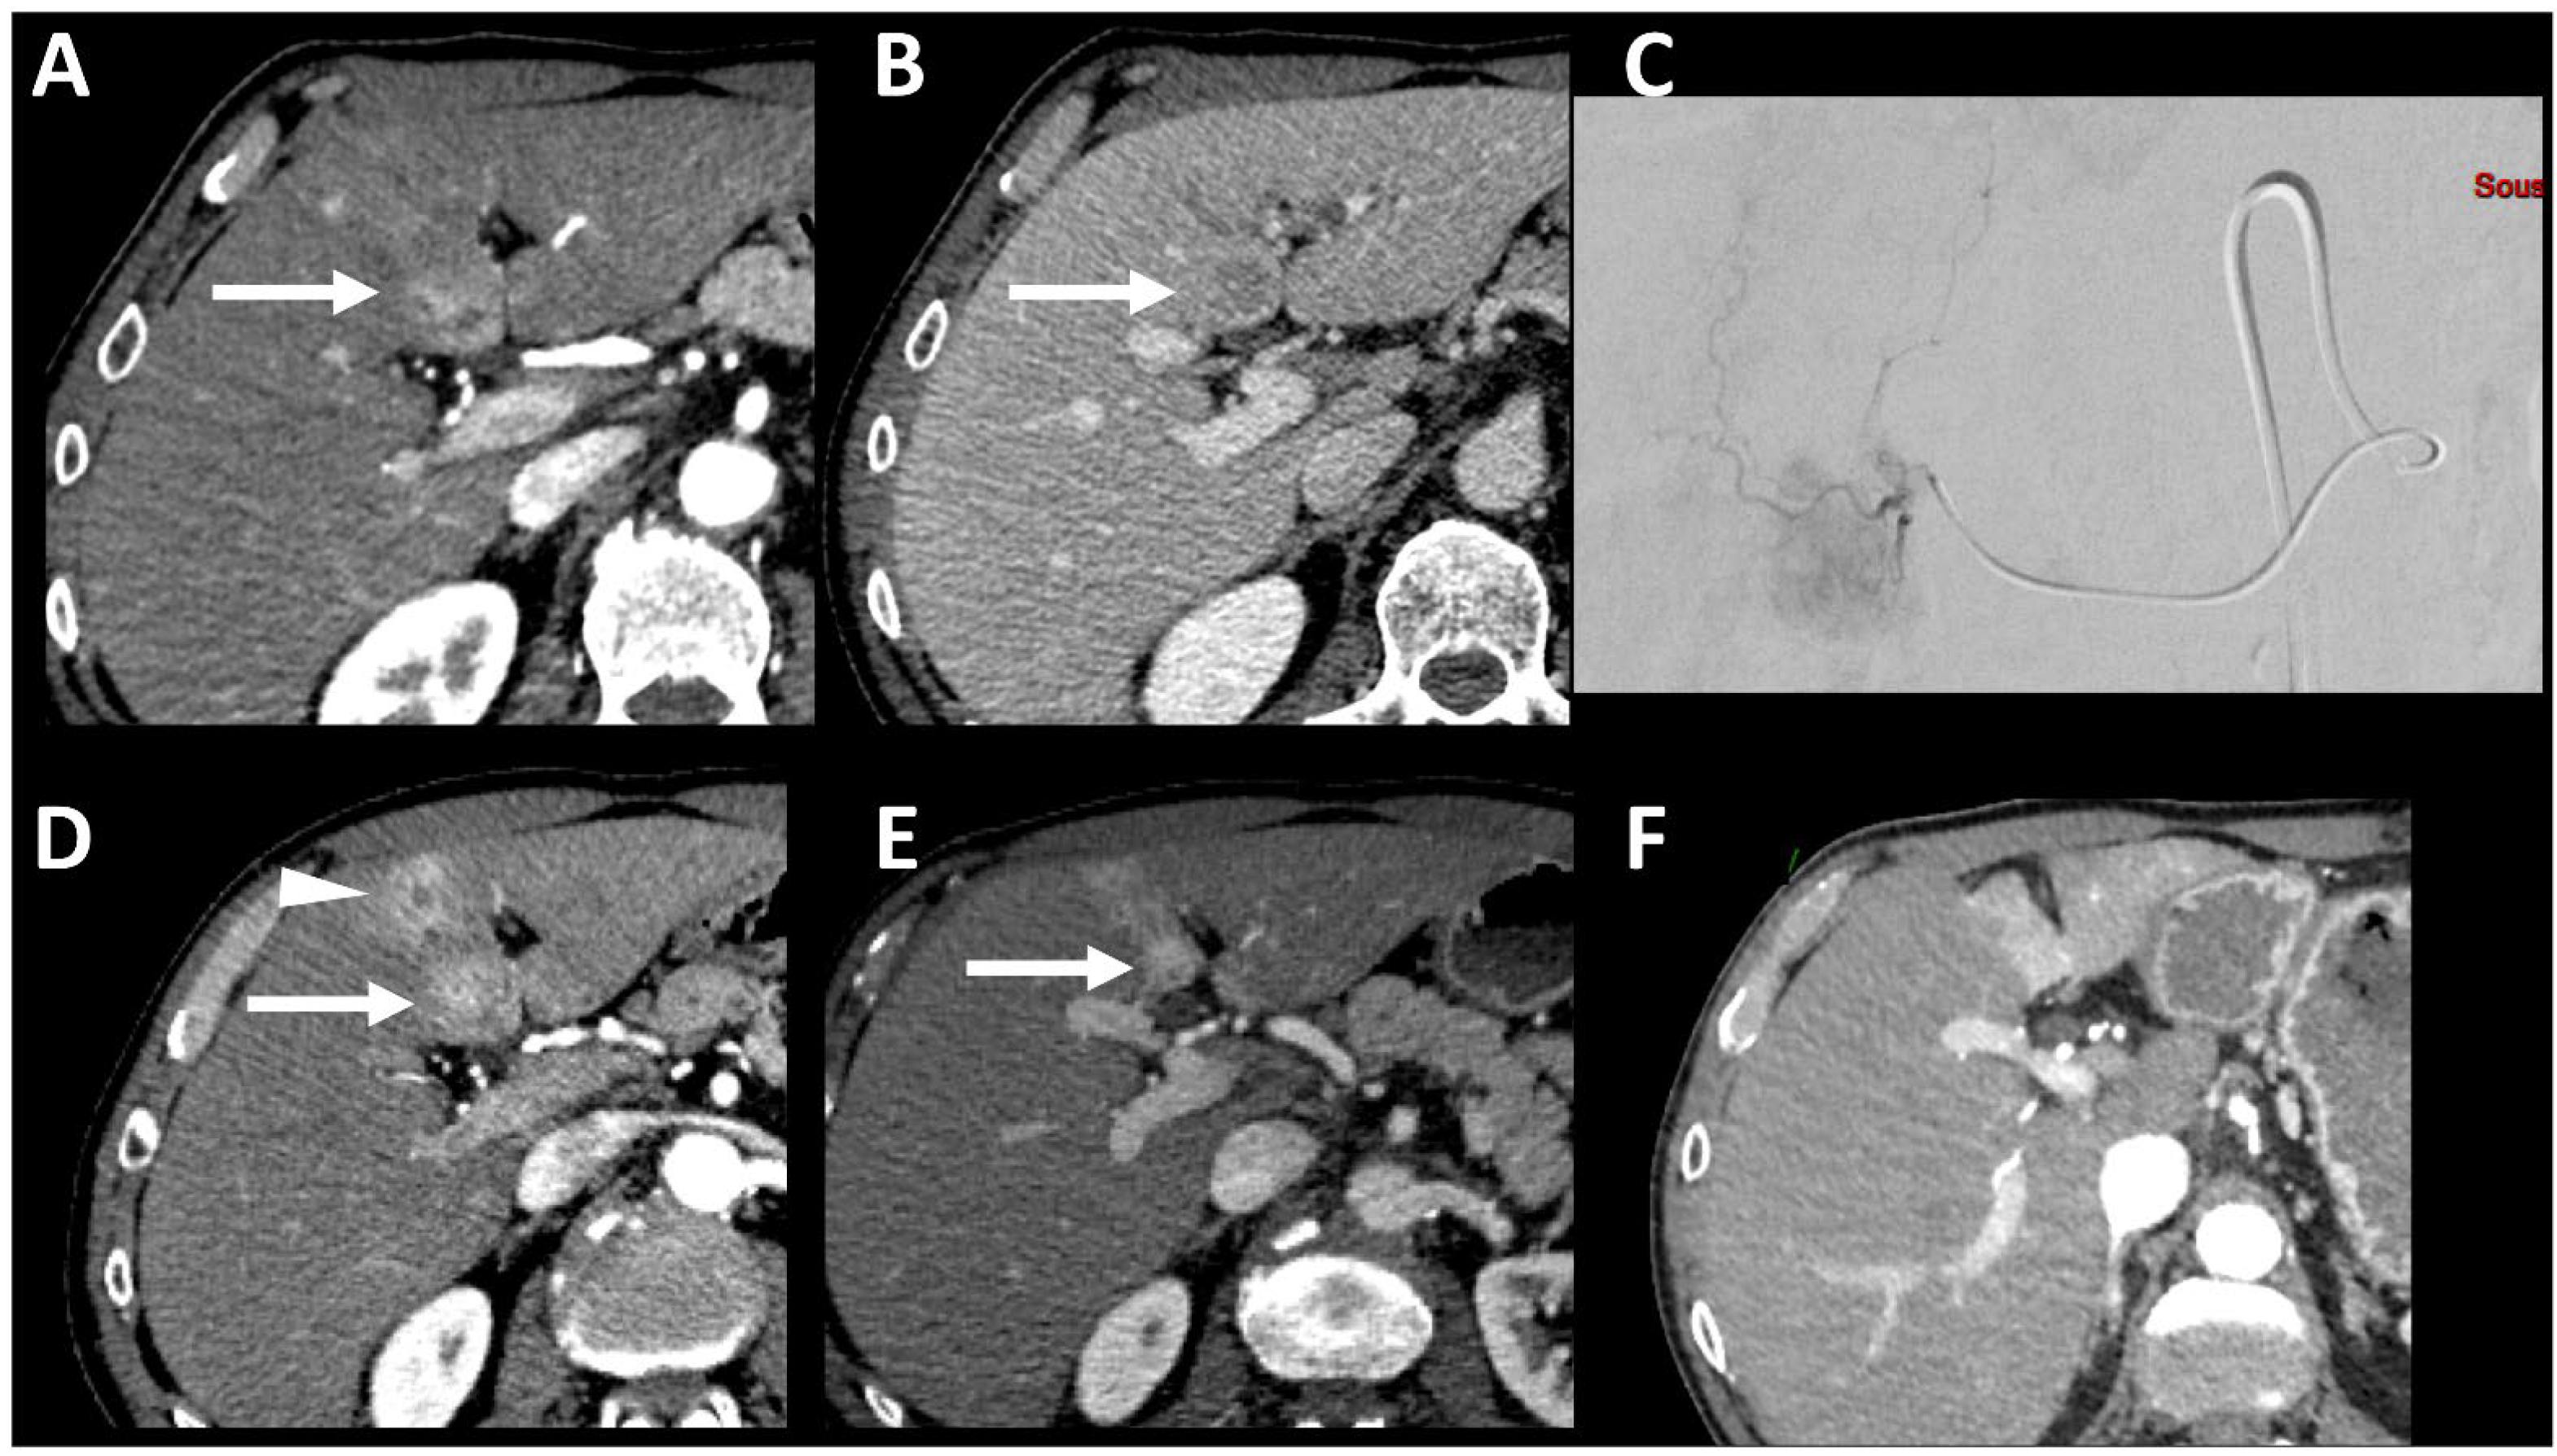

- Mendiratta-Lala, M.; Masch, W.R.; Shampain, K.; Zhang, A.; Jo, A.S.; Moorman, S.; Aslam, A.; Maturen, K.E.; Davenport, M.S. MRI Assessment of Hepatocellular Carcinoma after Local-Regional Therapy: A Comprehensive Review. Radiol Imaging Cancer. Radiol. Imaging Cancer 2020, 2, e190024. [Google Scholar] [CrossRef] [PubMed]

- Ibrahim, S.M.; Nikolaidis, P.; Miller, F.H.; Lewandowski, R.J.; Ryu, R.K.; Sato, K.T.; Senthilnathan, S.; Riaz, A.; Kulik, L.; Mulcahy, M.F.; et al. Radiologic findings following Y90 radioembolization for primary liver malignancies. Abdom. Imaging 2009, 34, 566–581. [Google Scholar] [CrossRef] [PubMed]